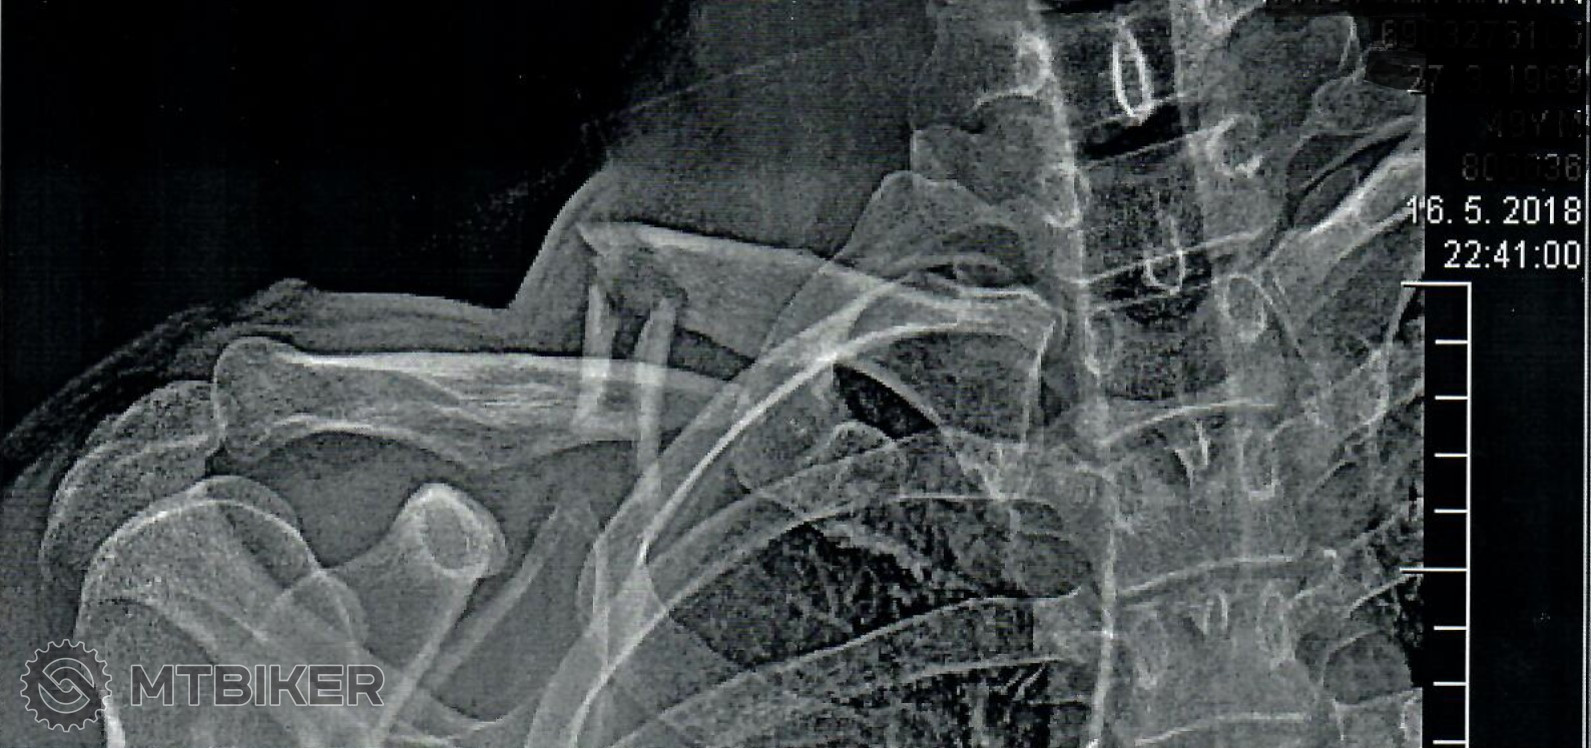

Hentek skok zo strechy nie .. a ten inak vazi tiez tipujem dobre cez 3kg. Ak nie viac .. narazam napr. na jeden typ hlinikovych Canyonov, ktore praskali po opreti. A tusim aj ten tvoj ram moc nevydrzal, ci ?